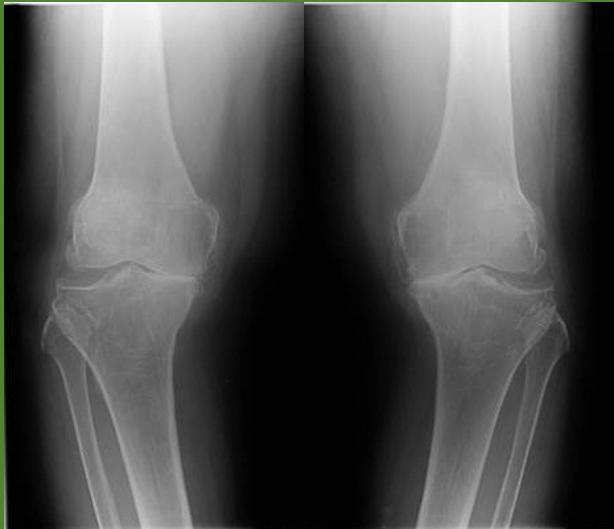

| Compartment Syndrome | Increased pressure within a closed fascial compartment, leading to reduced tissue perfusion, hypoxia, and irreversible muscle and nerve damage. Causes: Fractures (especially tibia/forearm), severe soft tissue trauma, arterial injury, burns, tight casts/dressings, post-ischemic reperfusion swelling, IV fluid extravasation, and bleeding disorders (e.g., hemophilia). High-Risk Notes: Pain may be absent in altered consciousness, children (monitor analgesia response), polytrauma, sedated/epidural cases, or concomitant nerve damage. Open fractures do not always decompress pressure. Gross/Clinical: -tense, shiny leg swelling with blisters in compartment syndrome.Imaging: - Intraoperative fasciotomy | History/Symptoms: Pain out of proportion to the injury (e.g., a “bursting” sensation), which is not relieved by analgesia. Clinical Features (The 5 P’s): - Pain with passive stretch (early, key sign; e.g., ankle dorsiflexion for leg, wrist for forearm). - Paresthesia (early). - Palpable tense swelling (shiny skin, blisters: clear=mild, serosanguinous=severe, bloody=worst; dusky/pallor skin). - Pallor, Paralysis, Pulselessness (late, ominous signs; pulses often palpable until late). Investigations: Primarily a clinical diagnosis (high suspicion key). Compartment pressure measurement can confirm: absolute pressure >30 mmHg or Delta Pressure (Diastolic BP - Compartment P) ≤ 25 mmHg. | Initial: ABCs, supplemental oxygen. Remove all circumferential dressings, casts (bivalve to skin), and splints. Elevate the limb to heart level (not above; higher reduces inflow). Correct any hypotension. Surgical: Urgent Fasciotomy if no response within 1h or confirmed pressure (prophylactic in high-risk like major osteotomy). Release all compartments/skin with long incisions; debride necrotic muscle via 4C’s (early: pink/red, soft, contracts/bleeds on pinch; late: dark, firm, no response); preserve neurovascular. Wound open (bulky dressing/splint, VAC, or boot-lace gradual closure); repeated inspections x48h; coverage in 3-5 days (skin graft usual; flap if nerves/vessels/bone exposed). | Cellulitis, Deep Vein Thrombosis (DVT), Arterial occlusion, Severe soft tissue injury without compartment syndrome; equivocal cases in polytrauma. | Complications: Volkmann’s ischemic contracture (permanent deformity, weakness, sensory loss, chronic pain). Contraindications (Fasciotomy): Confirmed >48h (irreversible damage, high infection risk from dead tissue); crush injuries with already necrotic muscle. |